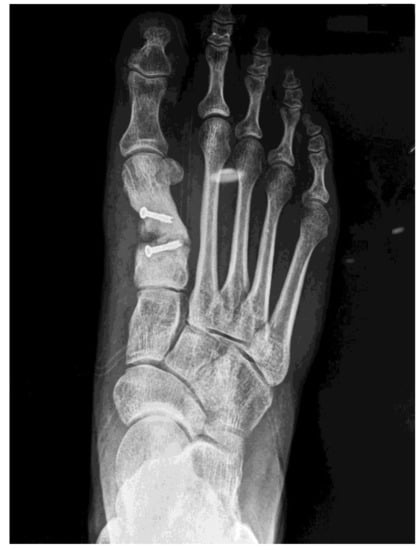

2. Case Report

2.1. Surgical Procedure

2.2. Postsurgical Procedure and Evolution

2.3. Results